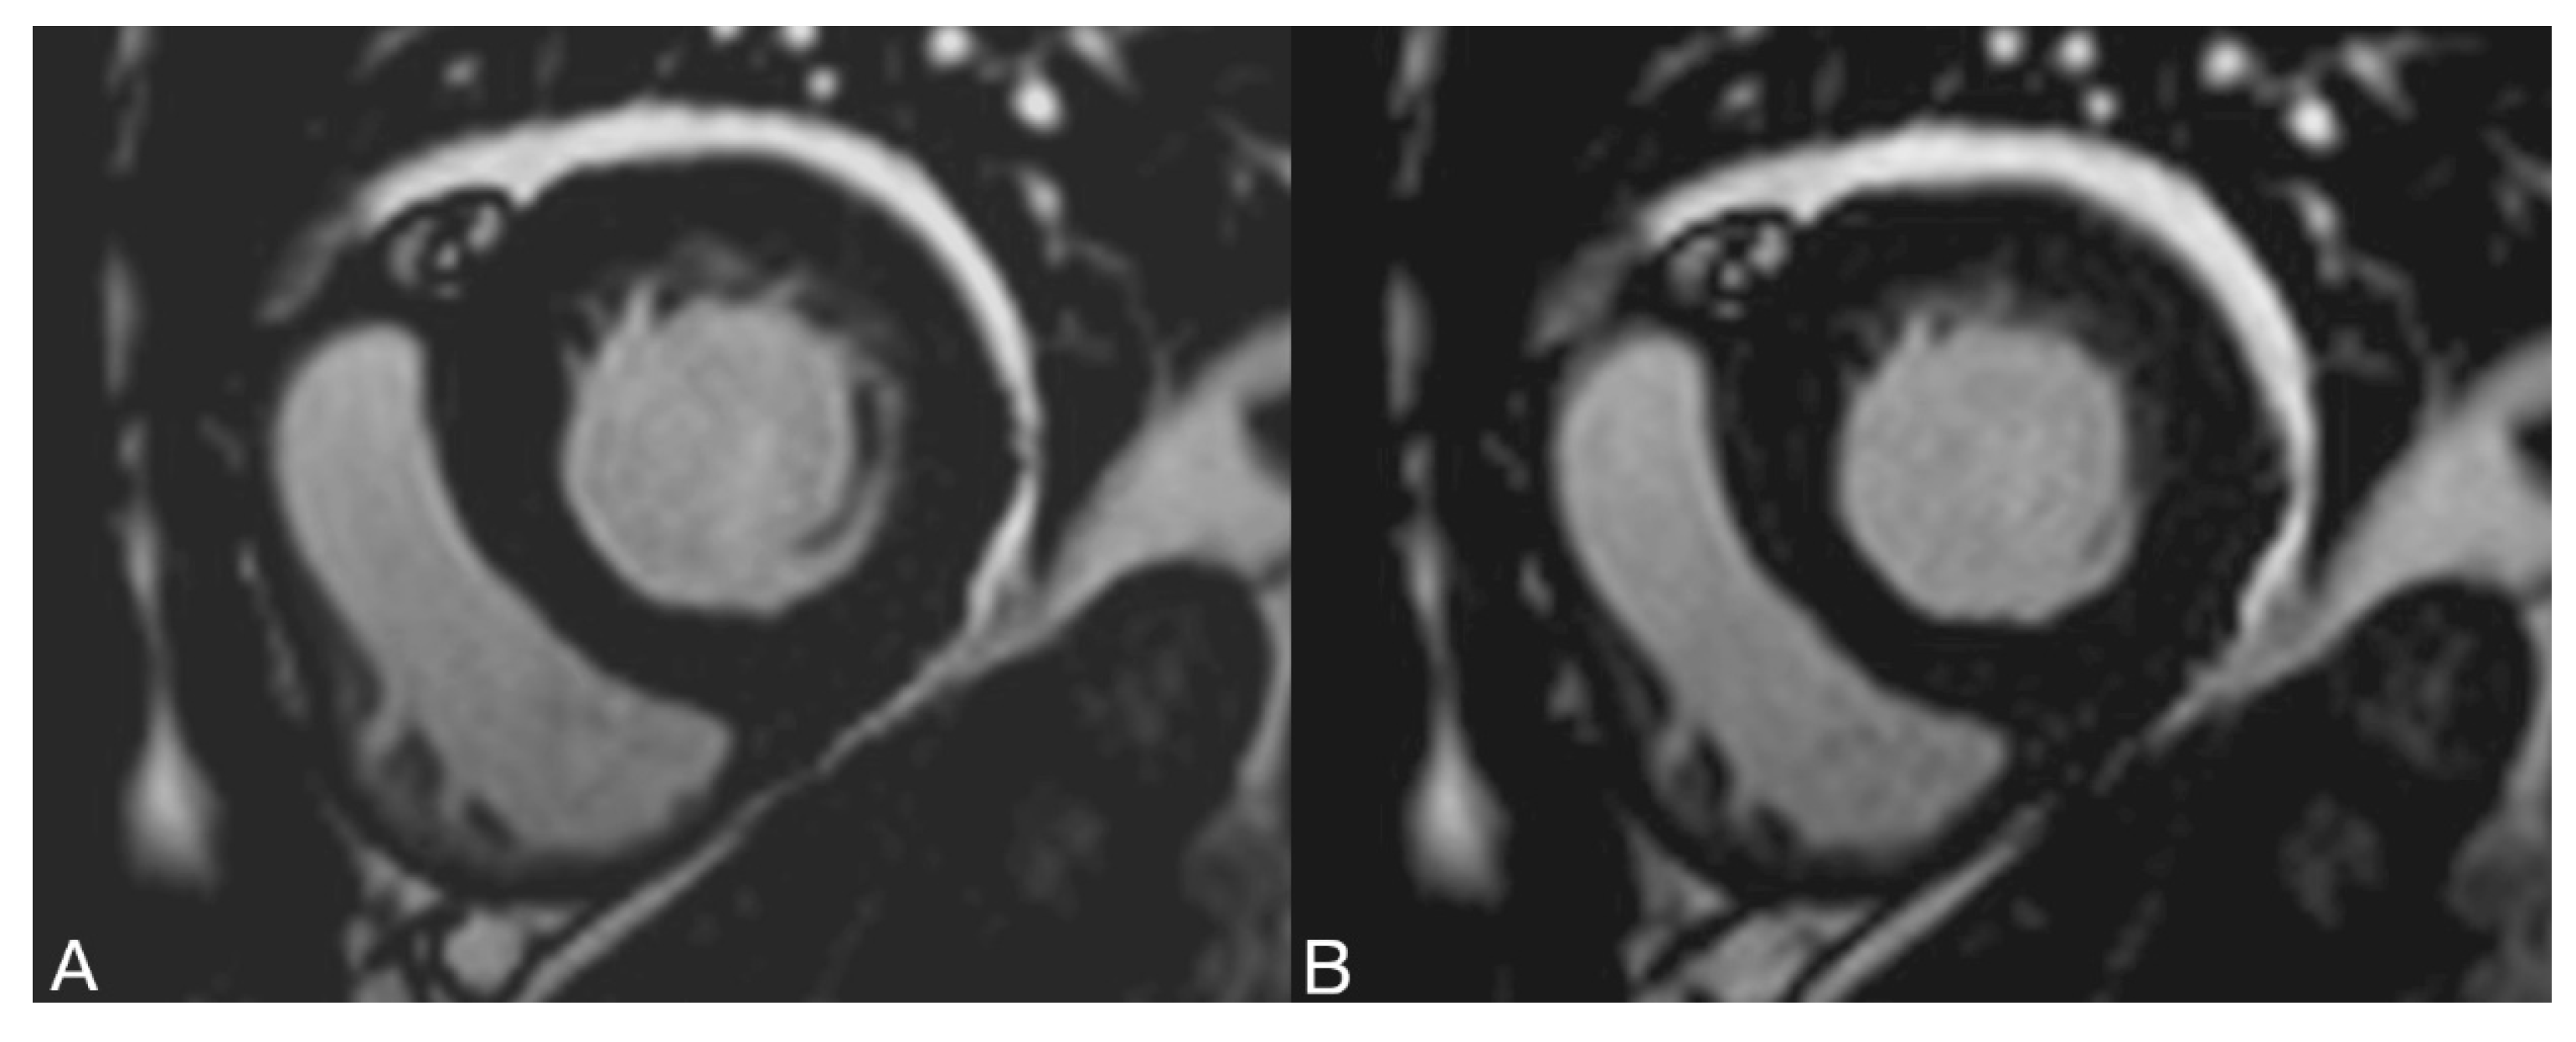

2.2.3. Volume Determination According to the Contour Surface Method (=KfM) with SyngoVia

2.2.4. Volume Determination according to the Contour Area Method (=KfM) with cvi42